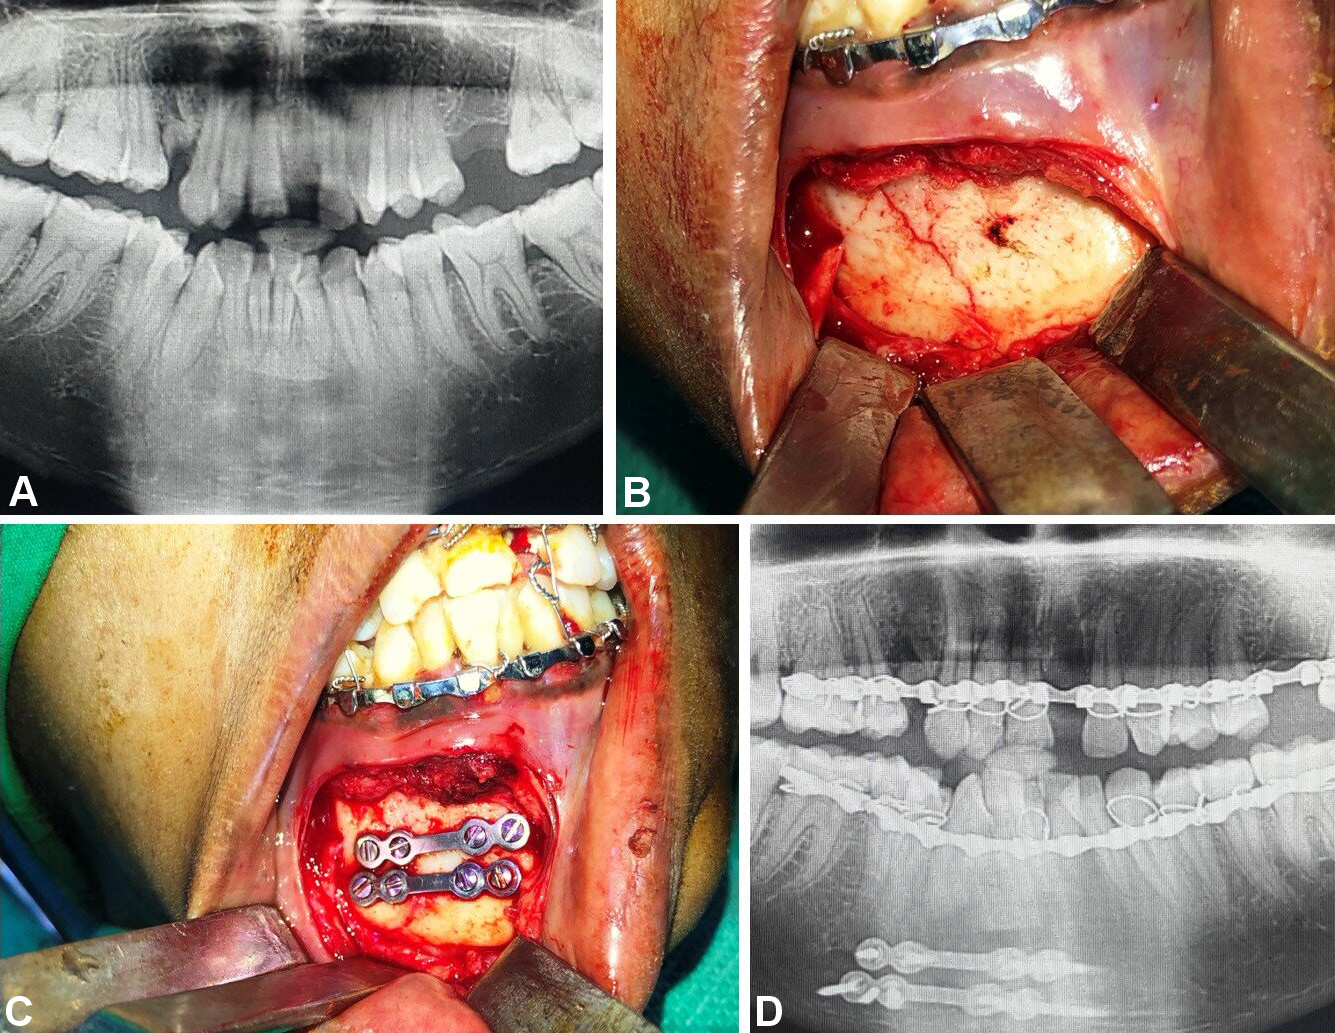

In group B, fixation was conducted using 2 titanium miniplates (2.0-mm, 4-hole design with a gap) and 8 miniscrews (2 mm × 8 mm and 2 mm × 10 mm), which were positioned subapically and at the inferior border of the mandible according to Champy’s lines of osteosynthesis (Figure 5, Figure 6, Figure 7).